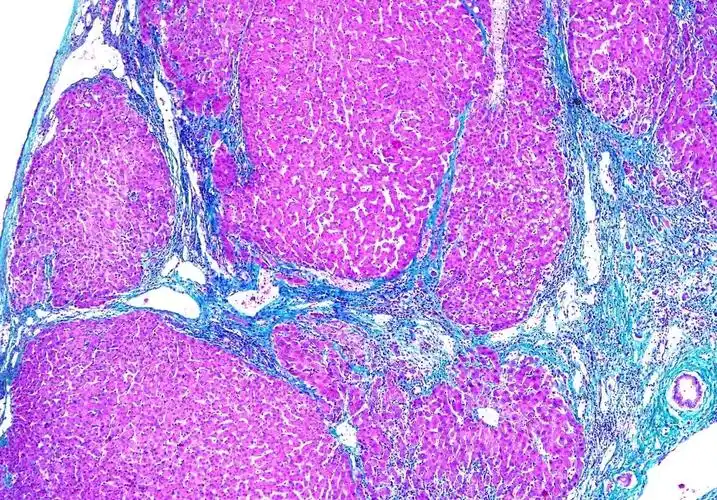

masson染色-肝脏肝硬化

肝硬化

门脉性肝硬化